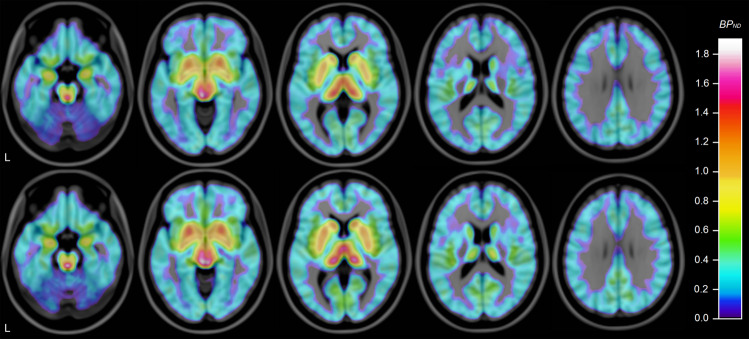

Fig. 2. Mean 5-HTT availability in ASD and control group.

Average of individual parametric images created using wavelet-aided parametric imaging [89], normalized to MNI-152 template using FSL 5.0 (FMRIB, Oxford, UK) and overlaid on MRI template. Subjects with ASD above, control subjects below. Horizontal slices, MNI coordinates (mm) z = −20/−8/4/16/28. “L” indicates left.

In the exploratory analysis, 5-HTT availability was found to be numerically lower in brainstem and all 18 examined subregions of gray matter in the ASD group, with the most marked differences in brainstem, striatal, and cortical areas, where 11–27% lower BPND was seen. Differences were statistically significant at the α = 0.05 level in brainstem and 9 of the 18 subregions: neocortex, frontal cortex, parietal cortex, rostral middle frontal, insular cortex, anterior cingulate cortex, posterior cingulate cortex, nucleus accumbens, and putamen (Table 2, Fig. 2, Supplementary Fig. 1). All findings remained significant after correction for multiple comparisons (Meff = 14.04). Subgroup analysis of 5-HTT availability in males and females did not reveal a sex-specific effect (Supplementary Tables 2 and 3). In the additional voxel-based exploratory analysis, two significant clusters were found (Supplementary Fig. 2, Supplementary Table 4).